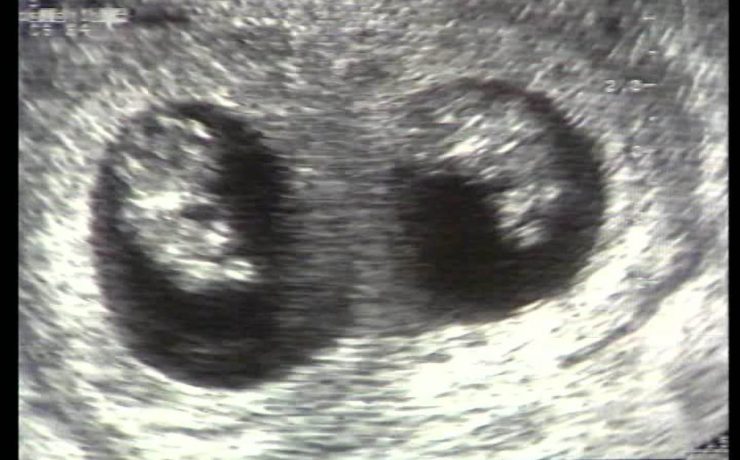

Revista Anales de Radiología de México. Ultrasonido Tiroideo en pacientes dediatricos del HIM, con diagnostico clínico de Tiroiditis de Hashimoto. México 2012 (11) – 1. Se revisaron 64 pacientes, por US más frecuente en mueres 9/1, y la lesión común es nódulo único, hipoecogénico, con contenido sólido, con vascularidad periférica.